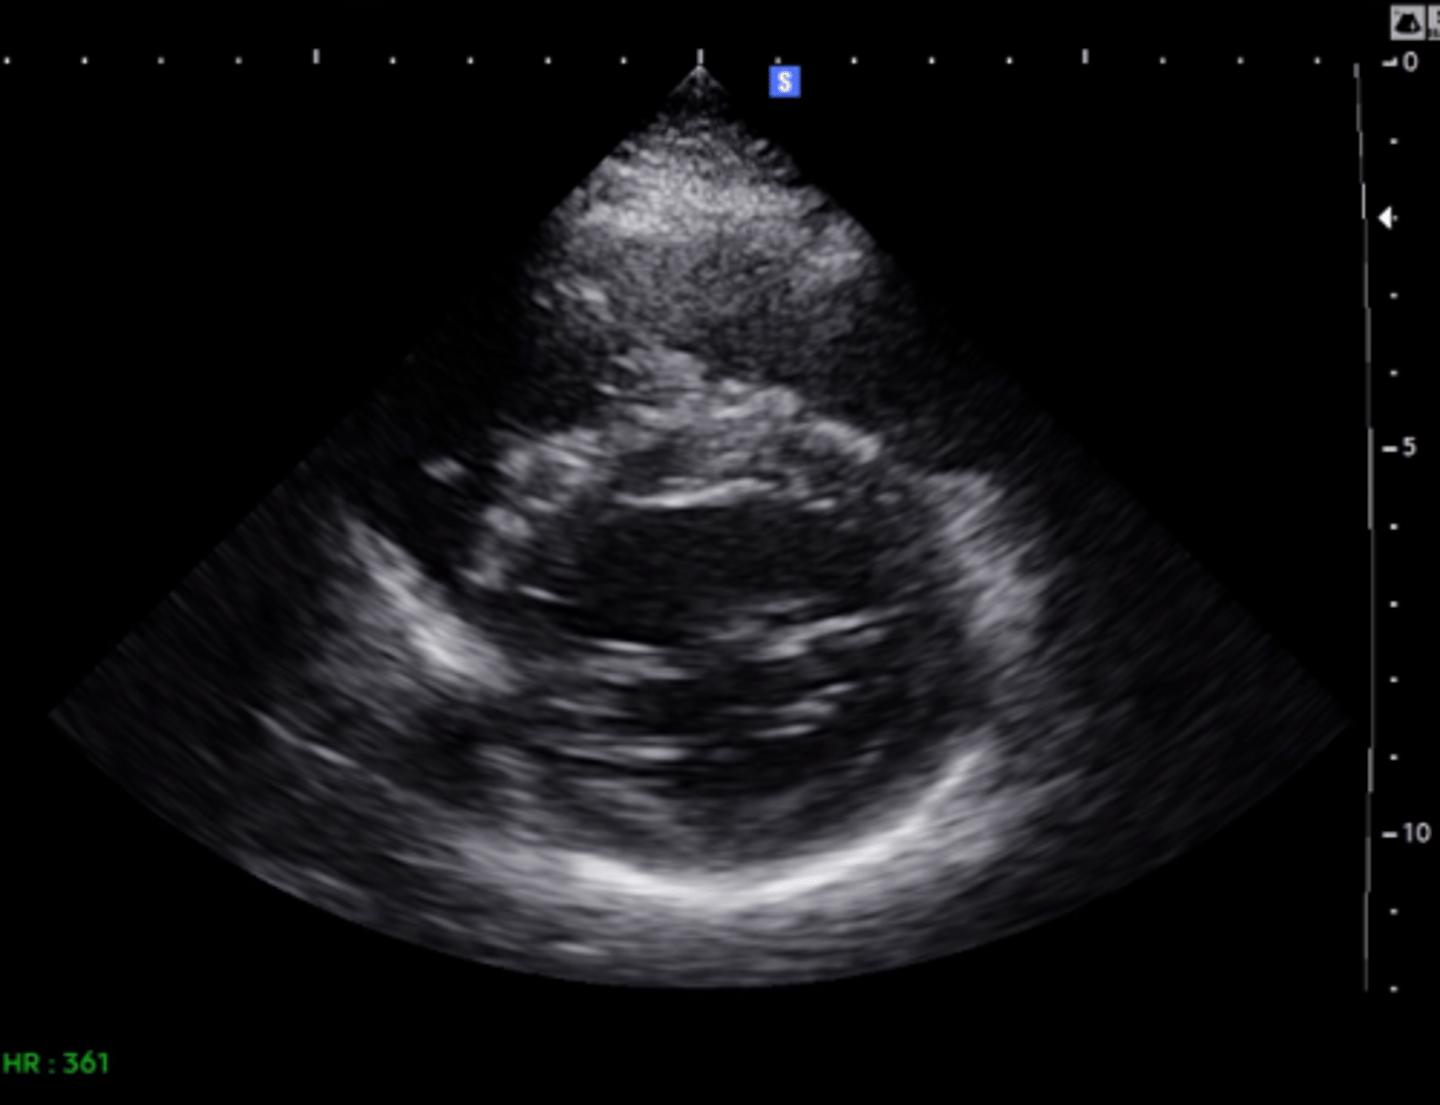

MV PLAX (top leaflet)

AMVL

MV PLAX (bottom leaflet)

PMVL